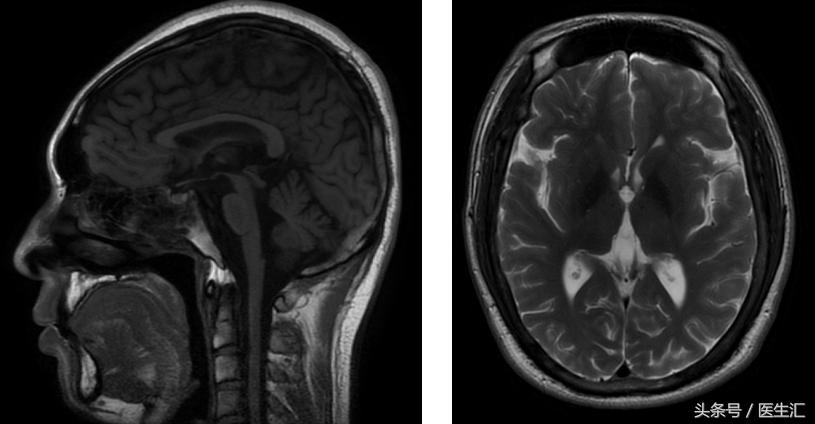

图像资料

定位:锥体外系(震颤)、小脑(步态、共济运动、影像学)

核磁:小脑萎缩、脑干萎缩

诊断:肝豆状核变性